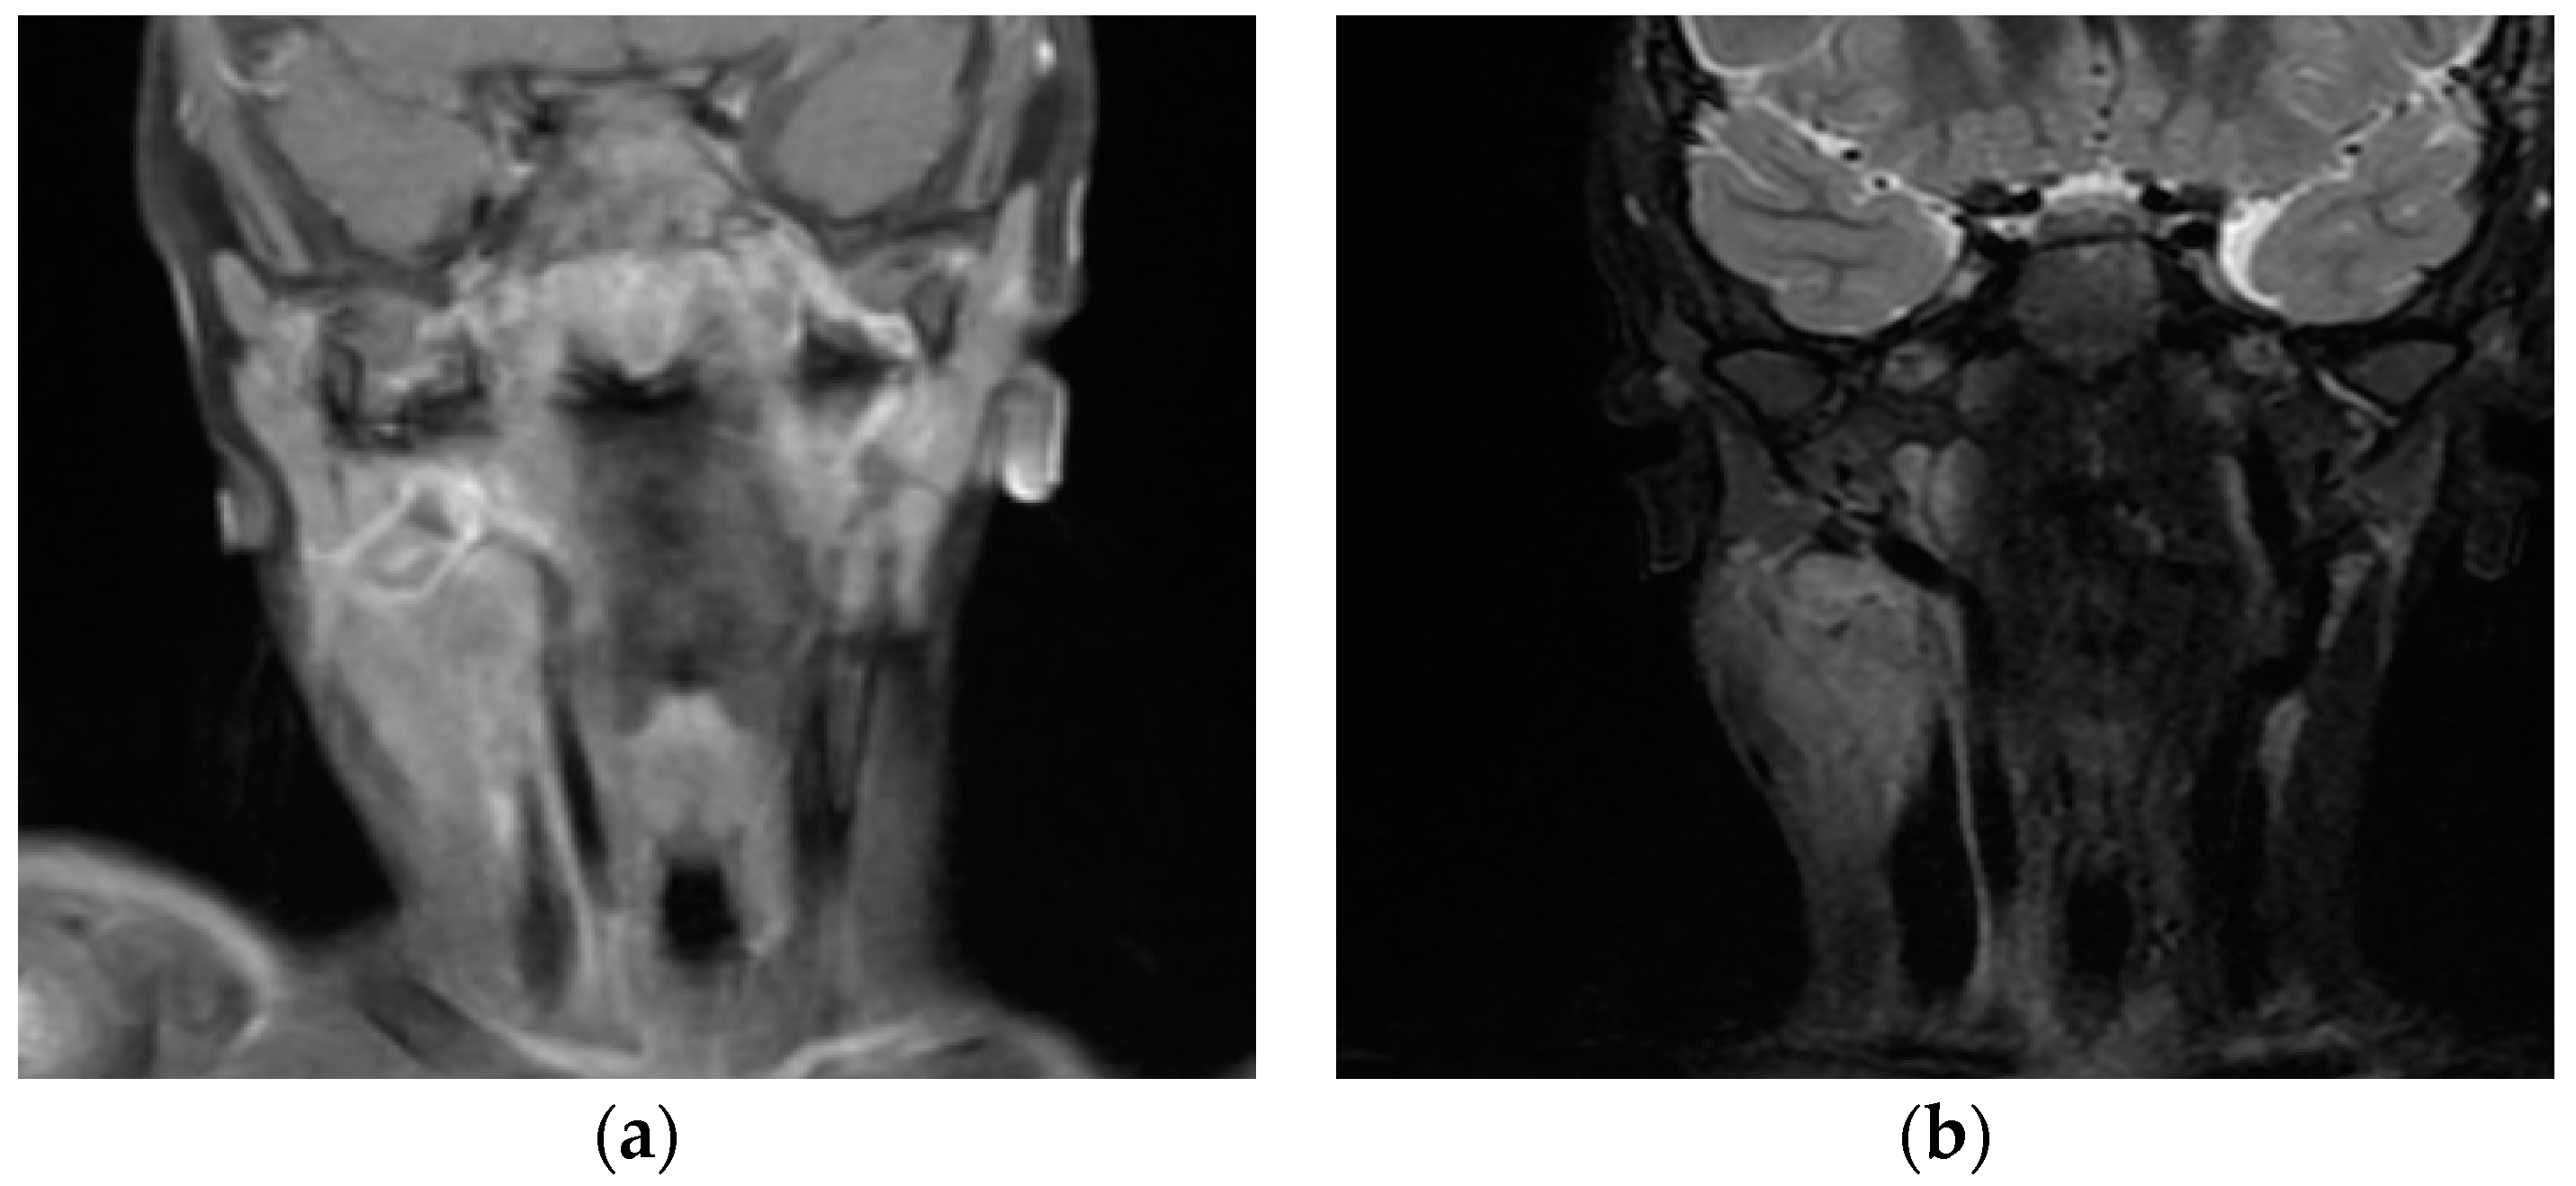

2. Case Report